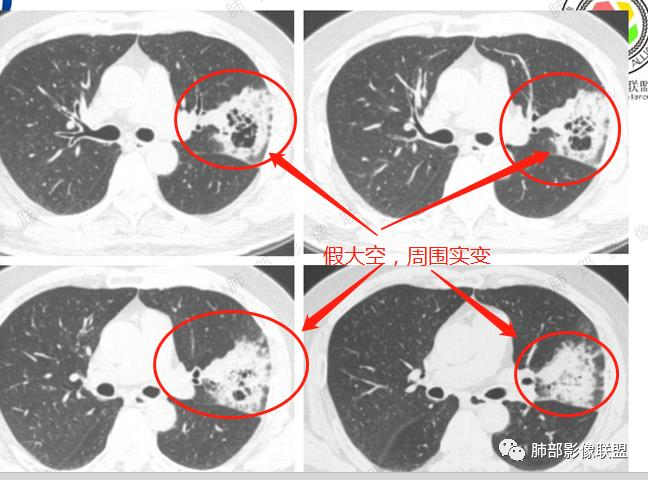

影像所见:左肺上叶尖后段团片状高密度影,边界清楚,其内密度不均,中心呈多发低密度影,与支气管关系显示不清。

边界清,假大空,粘液密度。粘液腺癌。

综上,左上肺假大空肿块伴周围实变,边缘似见粘液成分,胸膜牵拉凹陷,但收缩力偏弱,抗感染后两月复查,整个肿块增大,周围实变区增厚。符合腺癌(普通腺癌伴粘液分泌或粘液腺癌可能)

病理结果:腺癌(以粘液腺癌为主)

肺粘液腺癌